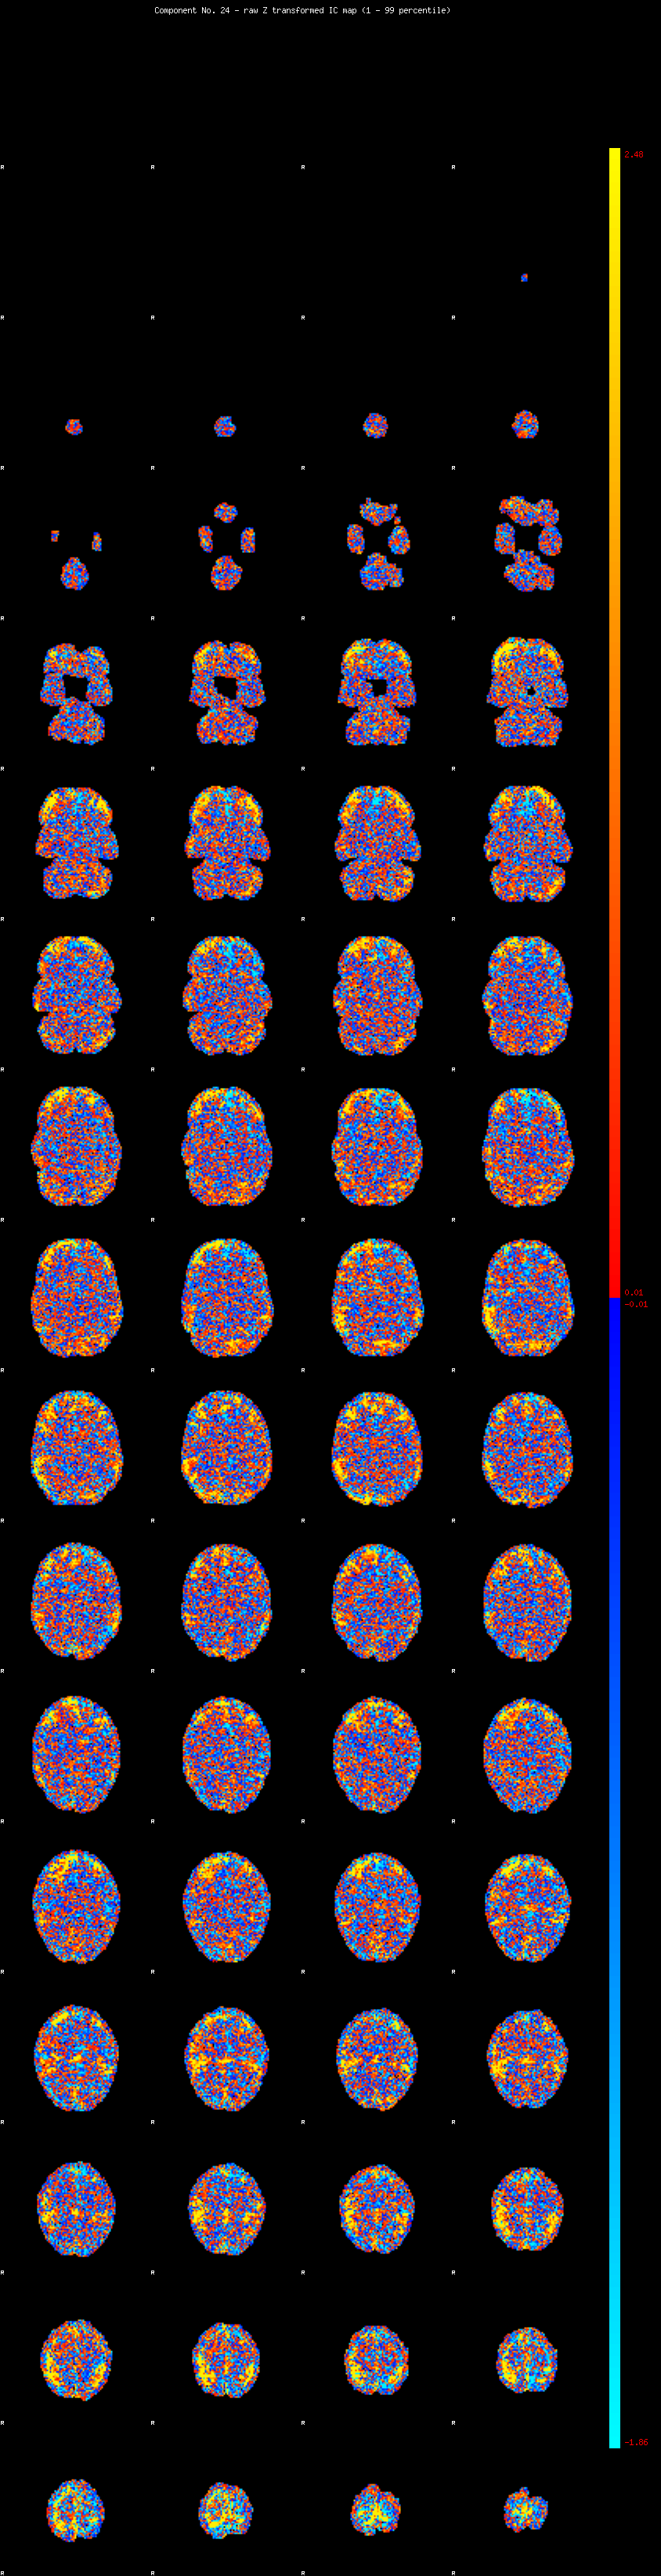

IC_24 Mixture Model fit

Means : 0.000000 4.005673 -2.660958

Vars : 1.000000 7.365442 1.481177

Prop. : 0.933162 0.049638 0.017200